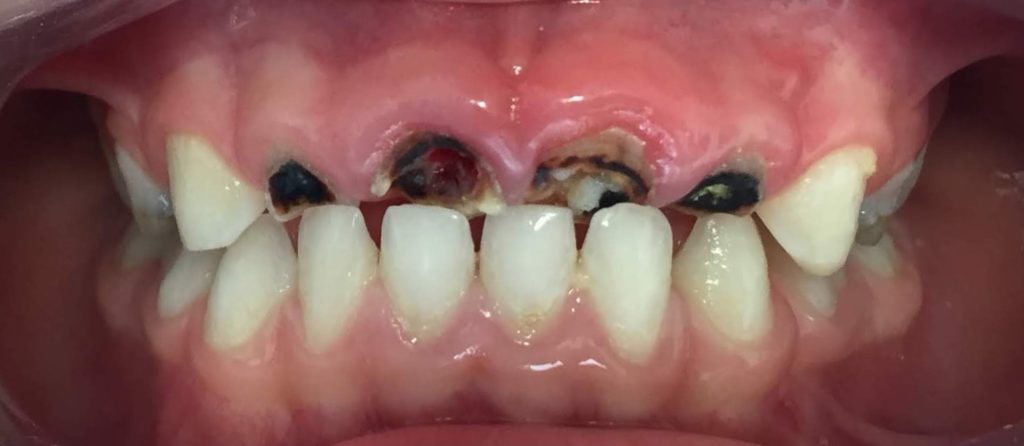

La caries de la infancia temprana o caries del biberón se produce cuando los dientes de un niño se exponen largos periodos de tiempo a líquidos azucarados, provocando un proceso destructivo por bacterias.

La CIT puede comenzar muy poco después de que salgan los dientes. Afecta por lo general a los dientes superiores de leche o primarios. Aparecerá en superficies lisas (caras bucales y caras linguales de los incisivos).

La velocidad de progresión es muy elevada y va destruyendo rápidamente los dientes. Para mirarlo hay que levantar de tanto en tanto el labio superior de los bebés.